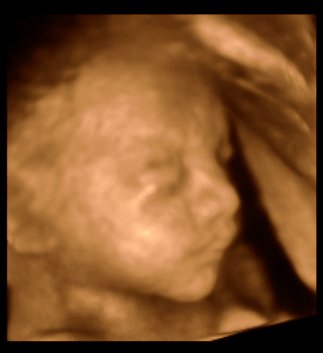

Da jeg snakkede med hende i dag sagde hun at fra uge 27 til og med uge 31 var det bedste tidspunkt at få det gjort....

Vi skal give 1400 kr for 45 minutters total gennem scanning, hvor hun fortæller, undersøger babyen fra top til tå, laver vægtskøn også får vi billeder og dvd med hjem.... Og ja det er da mange penge, men min forlovede har haft en masse vikar timer den her mdr, også sagde han at han syntes vi skulle bruge de penge på noget vi normalt ikke ville have gjort. Han sagde egentlig at jeg kunne gå ud og shoppe for dem, men jeg har termin om ti uger, så gider ærlig talt ikke bruge penge på nyt graviditets tøj, så hellere det her som vi egentlig havde valgt fra pga prisen, men som vi begge to rigtig gerne vil....